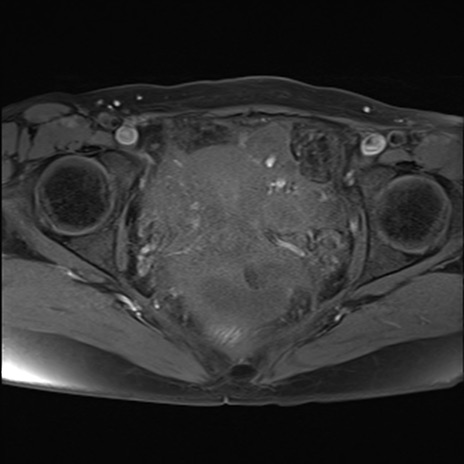

MRI(4日後)

T2WI(横断像)